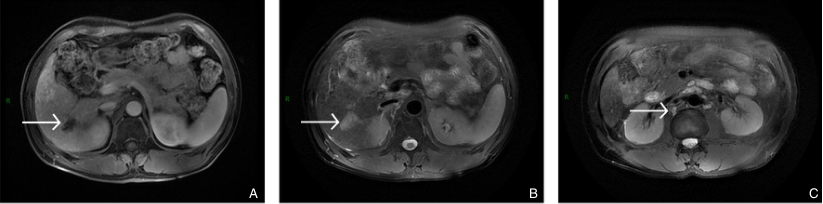

图2 患者转化治疗前MRI A-B:病变在T1加权成像(T1WI)中呈稍低信号,在T2加权成像(T2WI)中呈高信号;C:肿大淋巴结Fig.2